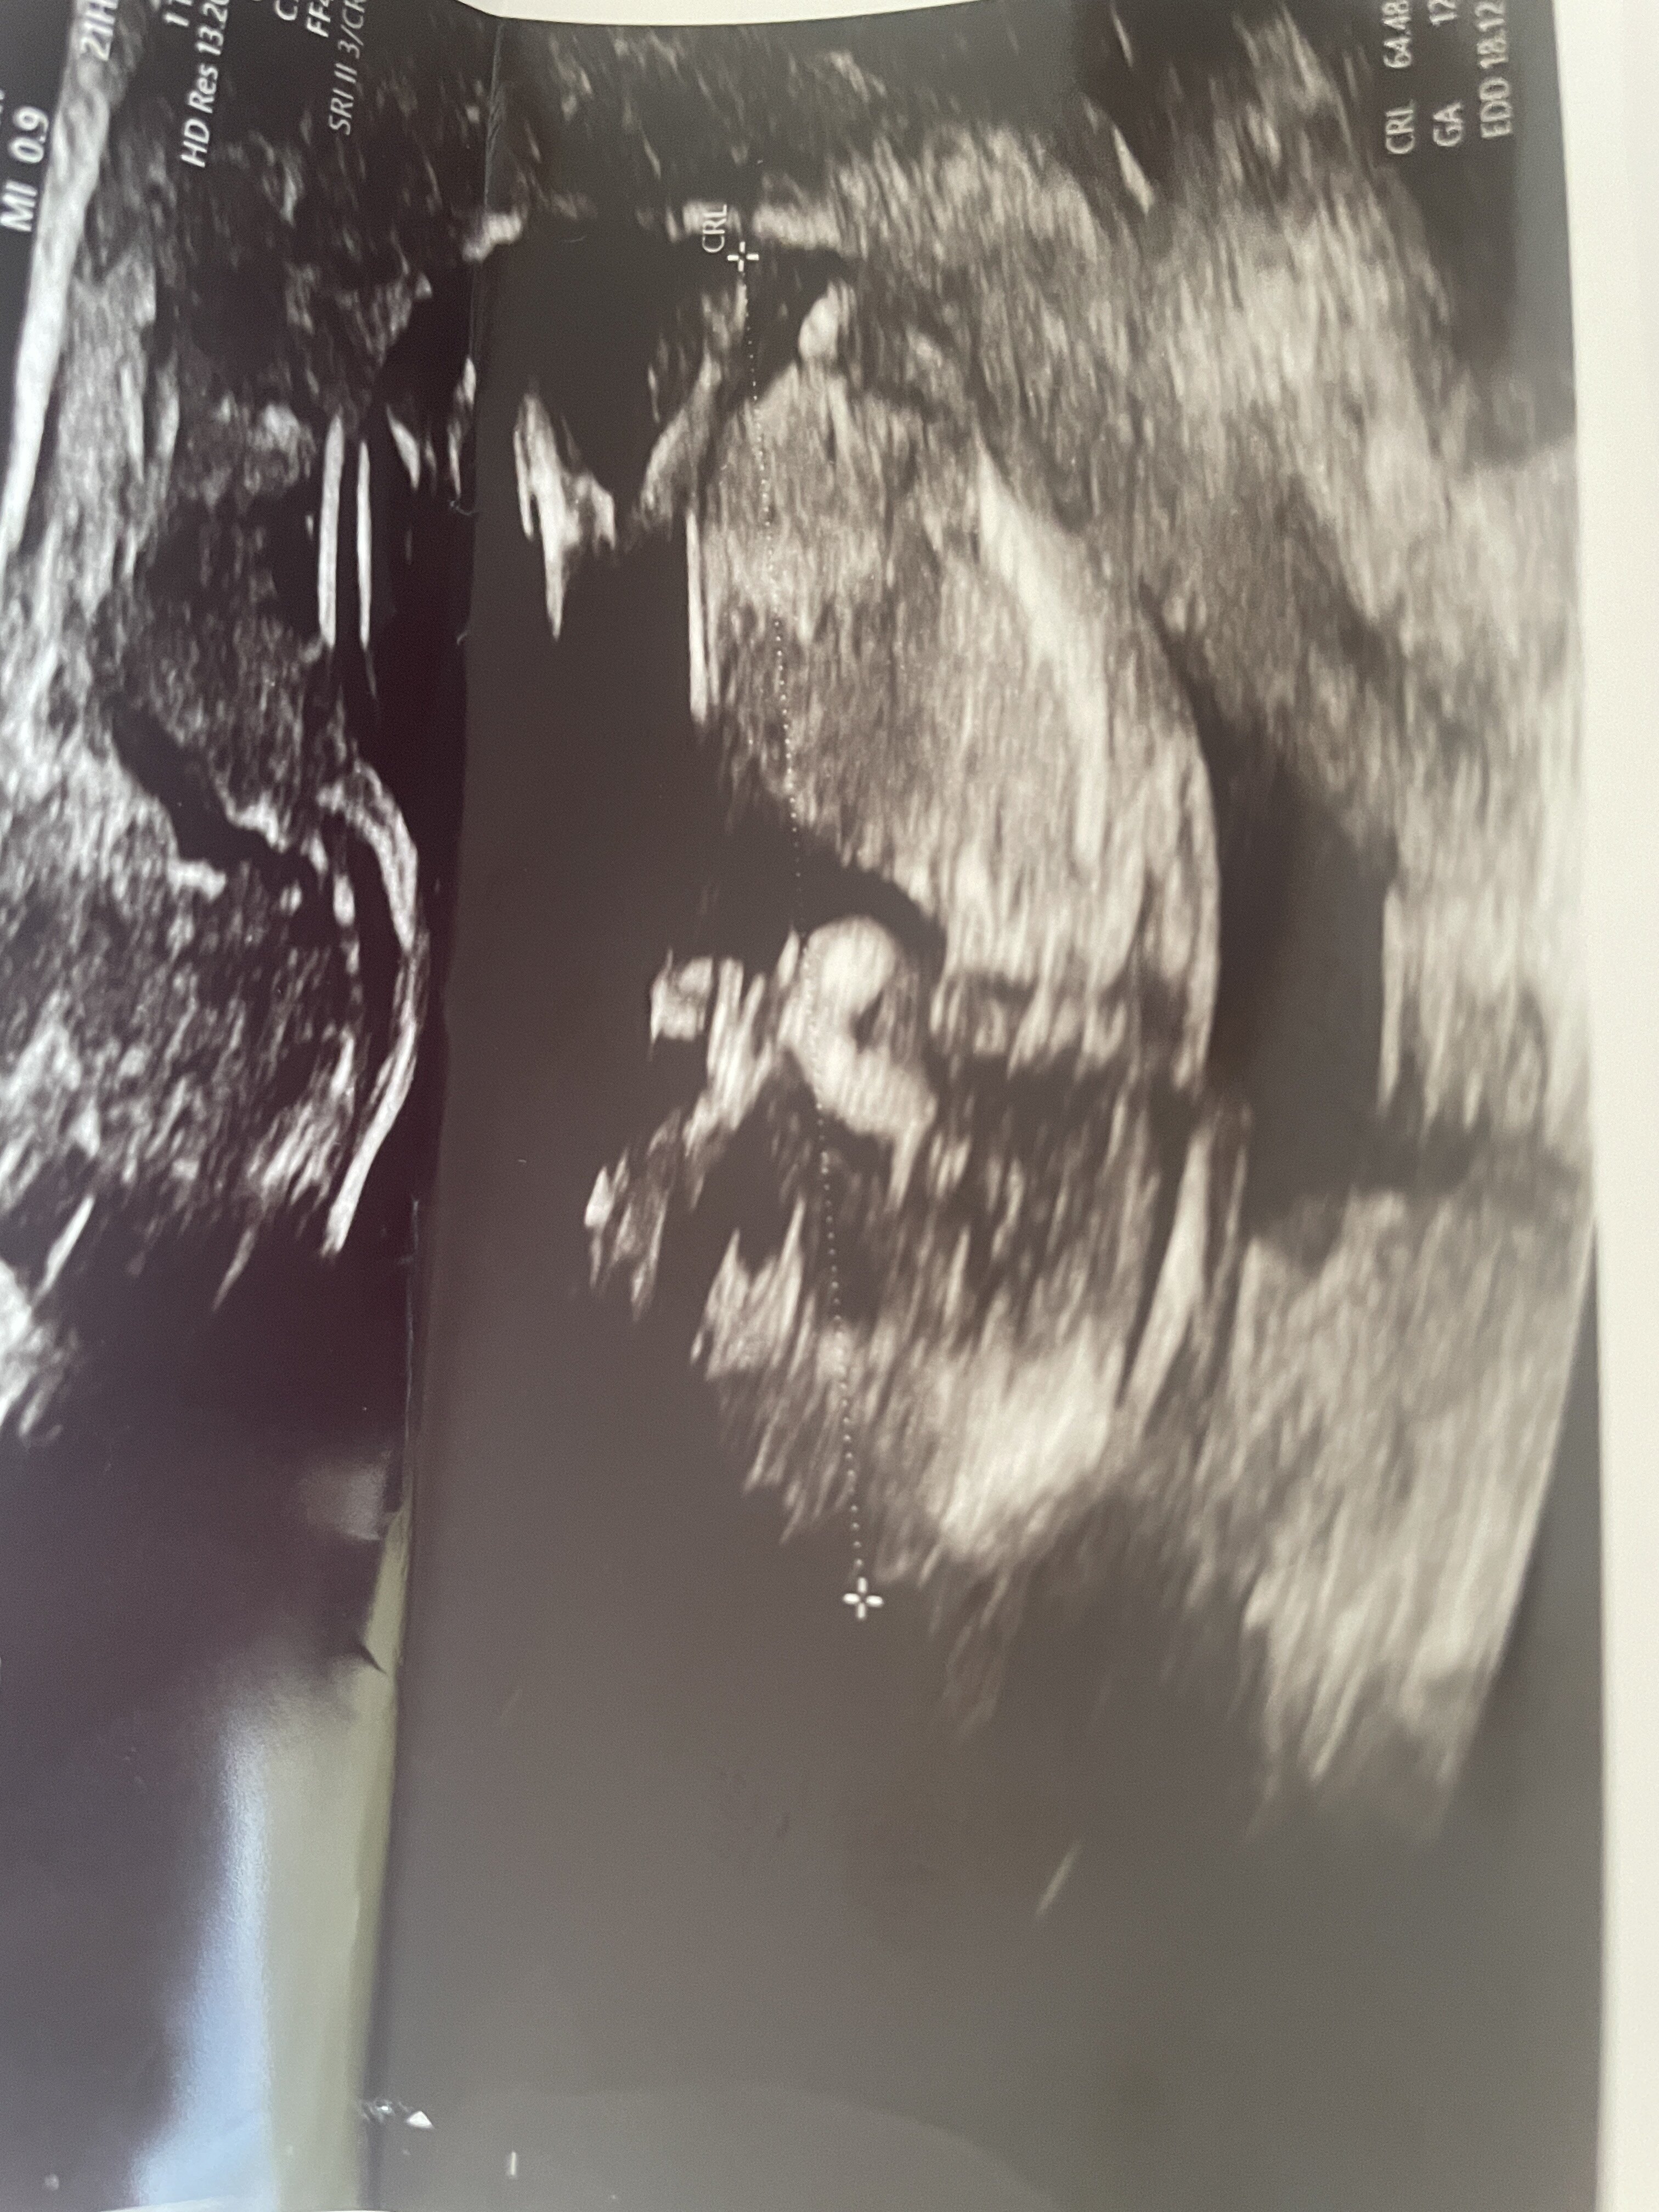

Zwracam się z pytaniem czy umiecie wskazać płeć dziecka na podstawie zdjęcia USG? Jestem w 13 tygodniu :)

• IMG_5903.jpeg

IMG_5903.jpeg

1,8 MB · Wyświetleń: 641

Takie „widełki” to na 70-80% dziewczynka, ale trzeba jeszcze poczekać, bo różnie to bywa jak się z wyrostka płciowego wykształcają docelowe narządy płciowe :)

No właśnie na prenatalnym gin powiedział że 60% chłopiec ale podświadomie czuje że to dziewczynka :) dziękuje za odpowiedź :)

Lekarz widzi więcej na usg niż tutaj z jednego zdjęcia, więc ciężko stwierdzić :) Ogólnie ta ocena wyrostków na tym etapie to trochę wróżenie z fusów. U syna się nie sprawdziło, u córki już tak :)